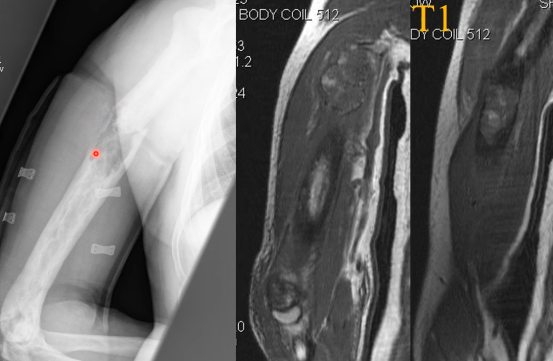

Bowing

Fractures

- Fractures Complètes et incomplètes

- Banana Fractures

Risque de transformation en sarcome

- Rare, 1% des patients

- Ostéosarcomes ++

- Fractures pathologiques avec régions de lyse exagerée

- RX: régions de Lyses progressive

- IRM: Remplacement médullaire